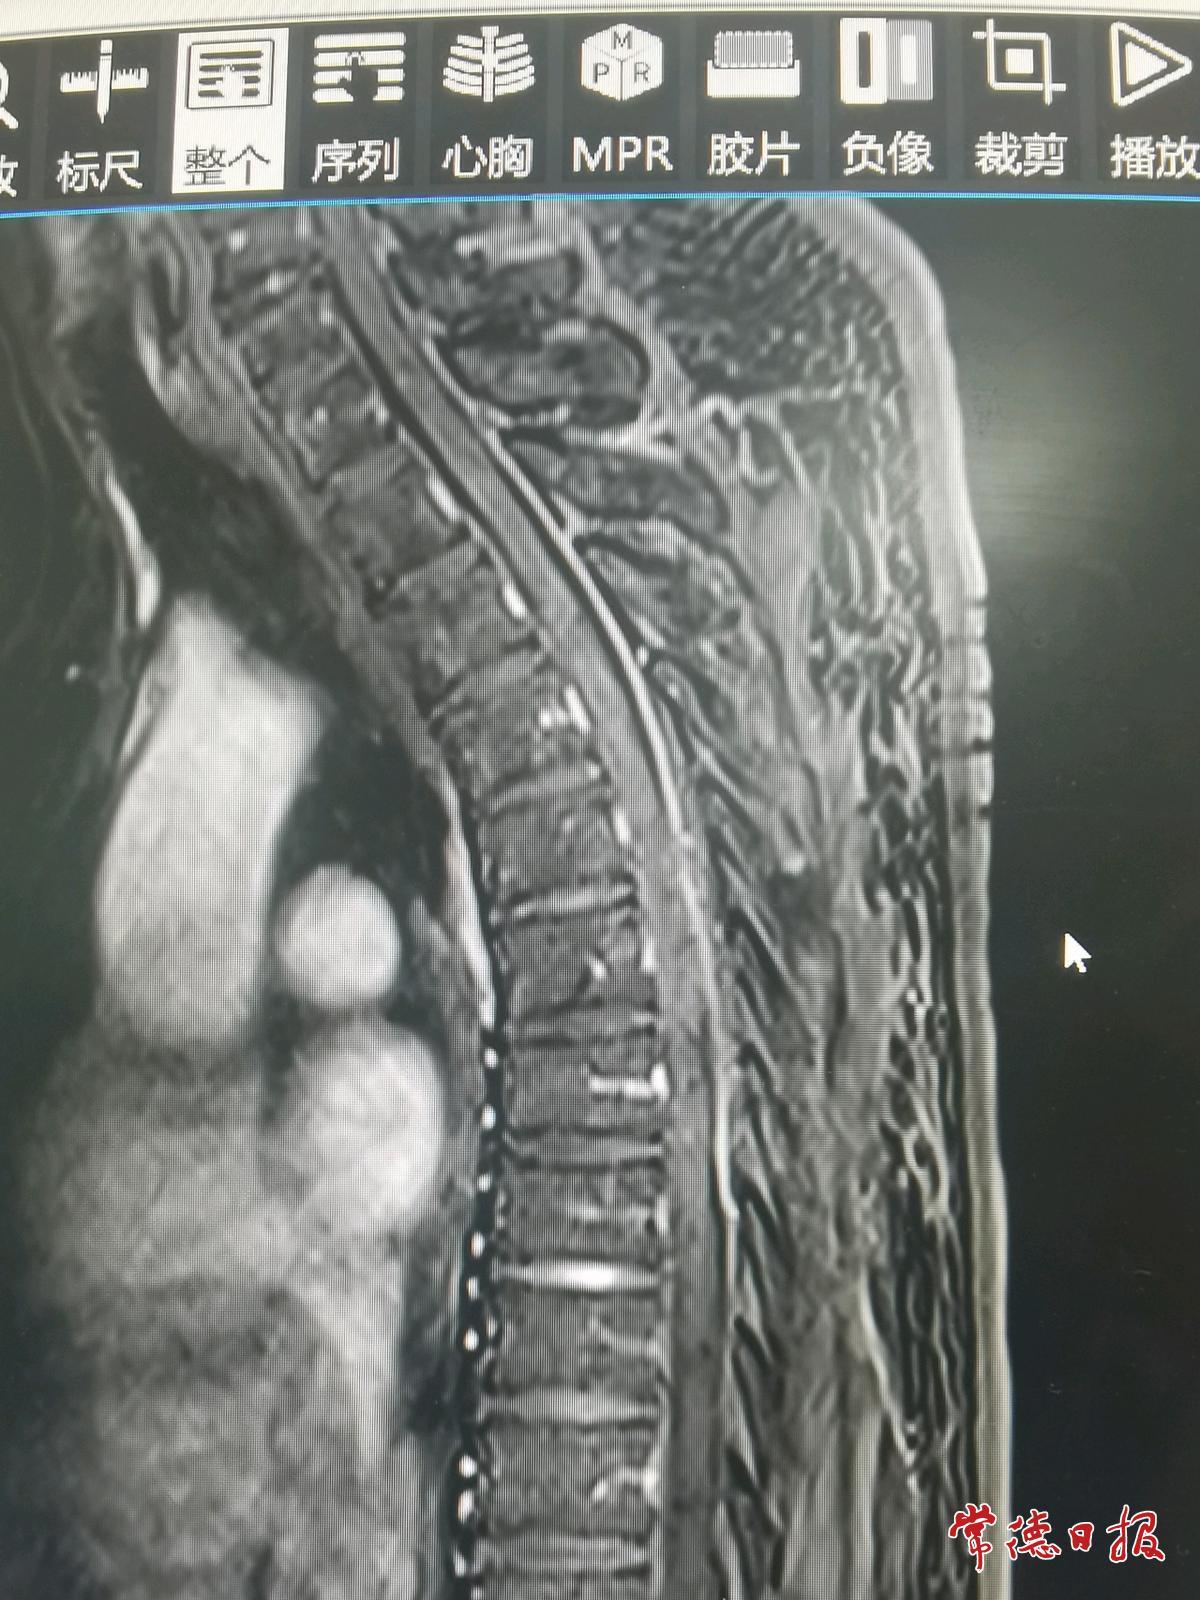

经磁共振检查,医生发现邓伯伯胸6-7椎管内长有一个血管瘤,属于脊髓肿瘤。正是肿瘤压迫神经,导致双腿功能逐步“失灵”。

针对邓伯伯的病情,吴孝才团队为其施行了显微镜下椎管内肿瘤切除术。手术切口小、创伤小,显微镜下可放大4至10倍,清晰显示肿瘤与周围组织的关系。术后经康复治疗,邓伯伯双下肢麻木、疼痛及肿胀基本消失,佩戴支具后可自主行走,生活基本自理。